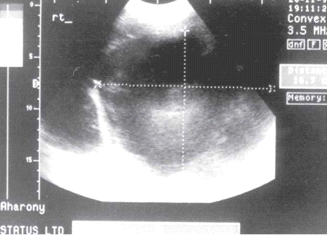

- באולטרה-סאונד אפשר להדגים גוש כיסתי. האולטרה-סאונד הפך לאמצעי האבחנתי החשוב בכיסיות של הכבד (תצלום 24.10).

בבדיקות מעבדה: תפקודי הכבד לרוב תקינים, אך תיתכן עליה קלה ברמת האנזימים. האבחנה מתבצעת על ידי טומוגרפיה ממוחשבת (תמונה 26.10 ) או תהודה מגנטית (תמונה 27.10) כך שבדרך כלל אין צורך לקחת ביופסיה. באולטרה-סאונד ניתן להדגים גוש בכבד (תמונה 28.10).

| תמונה 28.10 : הדגמה של FNH באולטרה-סאונד כבד. השנתות מצביעות על גודל השאת. |